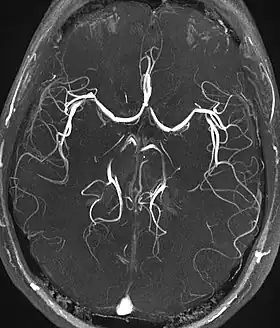

Magnetic resonance angiography (MRA) generates pictures of the arteries to evaluate them for stenosis (abnormal narrowing) or aneurysms (vessel wall dilatations, at risk of rupture). MRA is often used to evaluate the arteries of the neck and brain, the thoracic and abdominal aorta, the renal arteries, and the legs (called a "run-off"). A variety of techniques can be used to generate the pictures, such as administration of a paramagnetic contrast agent (gadolinium) or using a technique known as "flow-related enhancement" (e.g., 2D and 3D time-of-flight sequences), where most of the signal on an image is due to blood that recently moved into that plane (see also FLASH MRI).[51]

| Magnetic resonance angiography (MRA) and venography | Time-of-flight | TOF | Blood entering the imaged area is not yet magnetically saturated, giving it a much higher signal when using short echo time and flow compensation. | Detection of aneurysm, stenosis, or dissection[92] | ![]() |